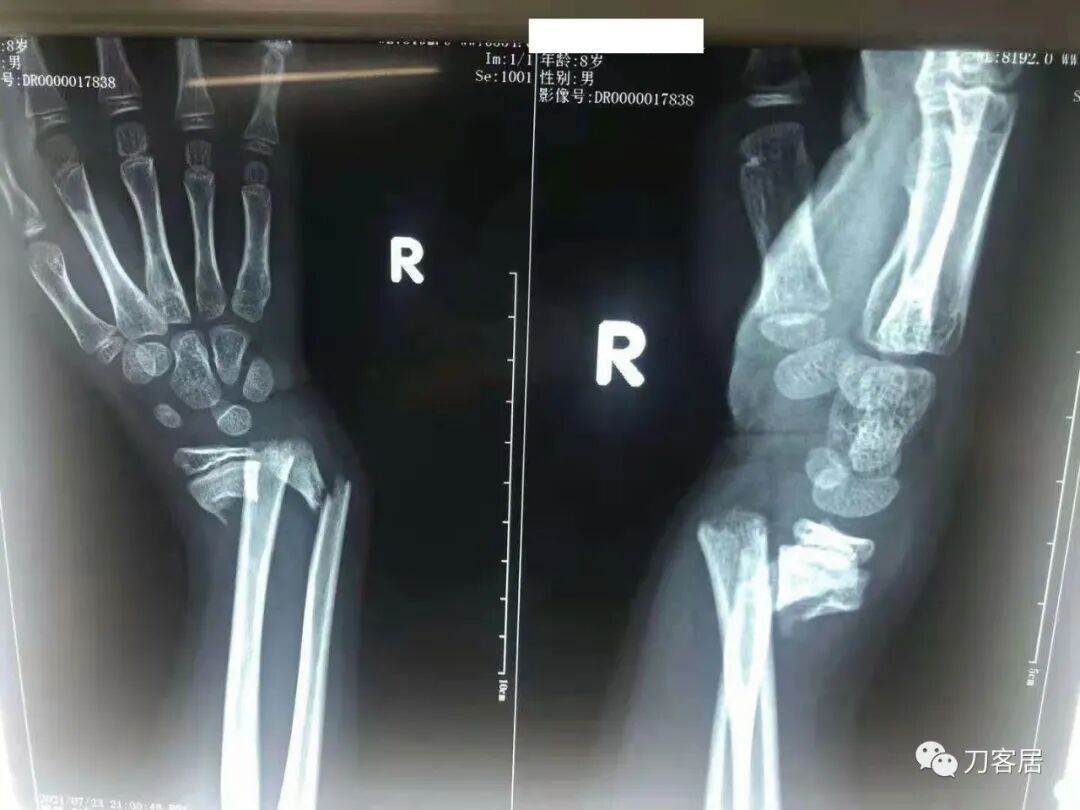

下面是这个6岁孩子,尺桡骨远端双骨折的术前及术后片子和外观照片。

1.  这是一个很简单的6岁儿童无移位的尺桡骨远端骨折。没有皮肤损伤,没有移位,没有骨折碎块儿。

2.  这个骨折处理起来也很简单,单纯的打石膏托或者中医的小夹板,或者正规的包括腕关节和肘关节的管型石膏外固定4周即可治愈该骨折。实在不行,如果这个孩子比较听话,不太调皮的话,用一本书,一个三角巾悬吊固定4周,都可以治愈该骨折。但是给这个患者用外固定架做了手术,而且桡骨远端的几颗克氏针距离骨折线太近,其中一枚克氏针进入到骨折间隙内。从这个术中图片来看,术者的外固定手术技术也有待于进一步的提高。毕竟术者应该还很年轻。从X线片来看,前臂及手的尺侧有不透光影,应该还使用了外固定石膏绷带托,而且我猜测应该是高分子的石膏绷带托,这个是纯属猜测,不一定是对的,不过如何解释前臂尺侧的不透光影呢?如果真是用了石膏绷带外固定的话,那为啥要做手术呢?外固定架术后就不该再用石膏绷带托辅助了。

这个病例,6岁的孩子,尺桡骨骨折在同一个平面,且都为小斜行骨折,不是螺旋形,不是粉碎性,不是成角移位性,属于稳定性尺桡骨双骨折,根本就没有任何手术的适应症。